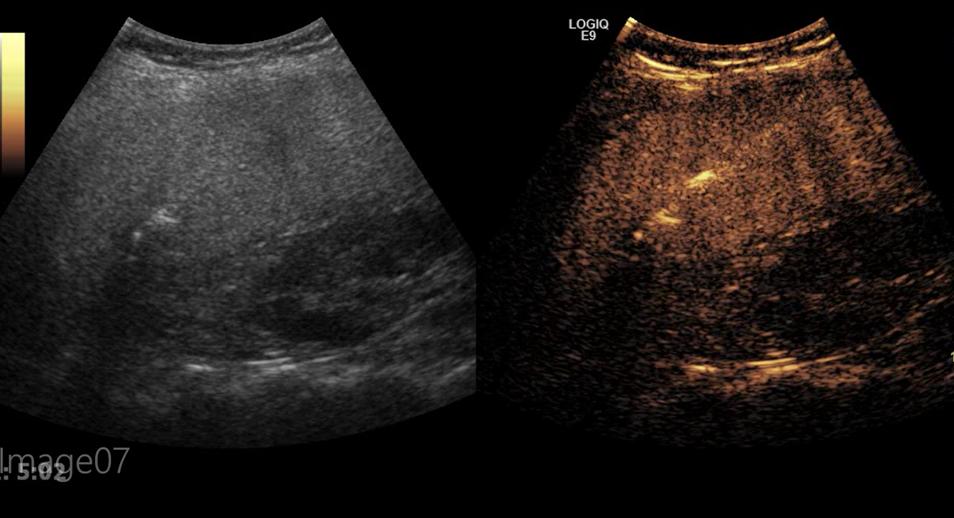

经过系统性化疗后的患者,肝转移灶减少及缩小,对于患者来说是个福音,但是对于超声介入的医生来说是个难题,因为化疗后转移灶明显萎缩,边界模糊,有的甚至在普通超声条件下与周围正常的肝组织表现相近,无法清晰的辨认肿瘤具体位置和范围,对于精准治疗是一个不小的挑战。因此超声介入组进行充分的术前讨论后,对患者进行了超声造影检查,超声造影作为血池示踪剂,能够精确而敏感地追踪肝转移灶,精确评估肝转移灶的数量、位置、范围,为术中提供精确定位及引导。

术前超声造影精确评估肝转移灶的数量、位置及范围